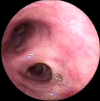

A 47-year old man visited our hospital because of purulent sputum for 3 months. Chest X-ray showed destruction of both the upper lungs, and bronchoscopy revealed inflammatory change with whitish plaque on the left main bronchus through upper division of the left upper lobe. Tracheobronchial aspergillosis (TBA) was finally diagnosed as a result of histologic and microbiologic examination. However, he went abroad without medication before the diagnosis was made and visited again 10 months later. Follow-up bronchoscopy showed complete regression of the previously noted endobronchial lesion. We describe this case to consider the role of antifungal treatment in immunocompetent hosts, as well as to discuss a rare condition; TBA resolved spontaneously.